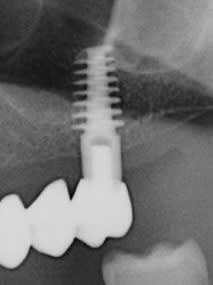

Je me décide enfin à venir vous demander votre avis sur ma pose d'implant du jour. Je les trouve un peu trop proche.. qu'en pensez vous? J'ai placé des Implants anthogyr reg 4*10 en 23 et 24. Trois couronnes solidarisées transvissées seront prévues sur 23-24-26.

Je les trouve surtout très infra osseux o_O Tu t'es trompé de repère sur tes forêts ou bien ?

Sinon si t'as 2mm entre les deux no problemo, ca sera juste pas facile de passer la brossette ;)

Plus sérieusement, c'est effectivement très, très infra osseux.

sont plutôt bien //....donc çà devrait aller...même si un peu trop enfouis...

par contre t'aurais pas oublié la vis de couverture sur celui en 24?

si oui, dépêche toi d'y retourner sinon le nonos va aller dedans et là, çà va être la merde à gérer...

Si c’est du 4 mm de largeur au niveau des deux implants PM . Il faut 3mm entre les bords des 2 implants. Soit 7 mm entre les 2 centres des 2 implants. Ça n’est qu’une estimation.

Effectivement , il sont un peu trop enfouis . Pour quelles raisons : mise en place des implants quelques semaines apres les extractions. J'ai voulu anticiper la résorption osseuse , peut être un peu trop . Je prendrais en compte vos réflexions lors de mes prochaines poses.

Il n'y avait rien à anticiper dans le sens vertical. Mais maintenant tu vas perdre de l'os parce qu'ils sont trop enfouis. Sinon oui ils sont un peu trop proches 😢. La distance idéale entre 2 implants est de 3mm.

Ils sont en effet légèrement trop sous crestal, solutions :

soit tu y retournes (, lundi tes radios sont du 10 ) et tu dévisses tranquillement de 2 tours,

soit tu avance la date de vis de cicatrisation

soit tu attends et il te faudra éventuellement gratter un peu d'os qui ne devrait pas recouvrir les vis de fermetures en principe si tu surveilles (radios).

éventuellement tu ne solidarise pas les couronnes pour une meilleur hygiène .

sinon c'est propre (axe)